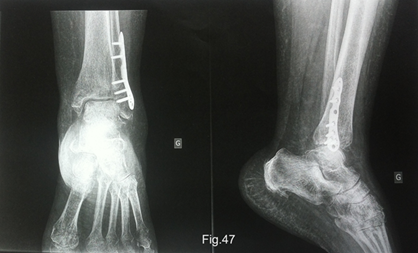

La radiographie montre que la fracture de la malléole externe est consolidée. Cependant, des signes d'ostéoporose pommelée (trabéculaire en forme de bulles) sont visibles dans le pied, c’est un signe typique de l’algodystrophie (Fig.47). Son chirurgien lui a prescrit une scintigraphie osseuse, avec un rendez-vous prévu dans dix jours. La scintigraphie osseuse permettra de confirmer le diagnostic d’algodystrophie.